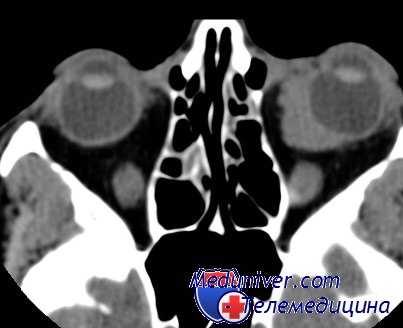

- Томография глазниц. На КТ орбит видны единичные или множественные объемные образования (1 крупная материнская киста и несколько дочерних меньшего размера) с четкими неровными контурами. Средний диаметр эхинококковой кисты не превышает 1 сантиметра.

В отдельных случаях киста разрушает стенку глазницы и распространяется в смежные лобную и верхнечелюстную пазухи, в полость черепа, кавернозный синус. Описаны случаи проникновения эхинококка в глазницу из других полостей. Проанализировав 10 случаев внутриорбитальной кисты, авторы пришли в выводу, что при применении компьютерной томографии черепа предоперационная диагностика более точна [Aouchiche M. et al.].